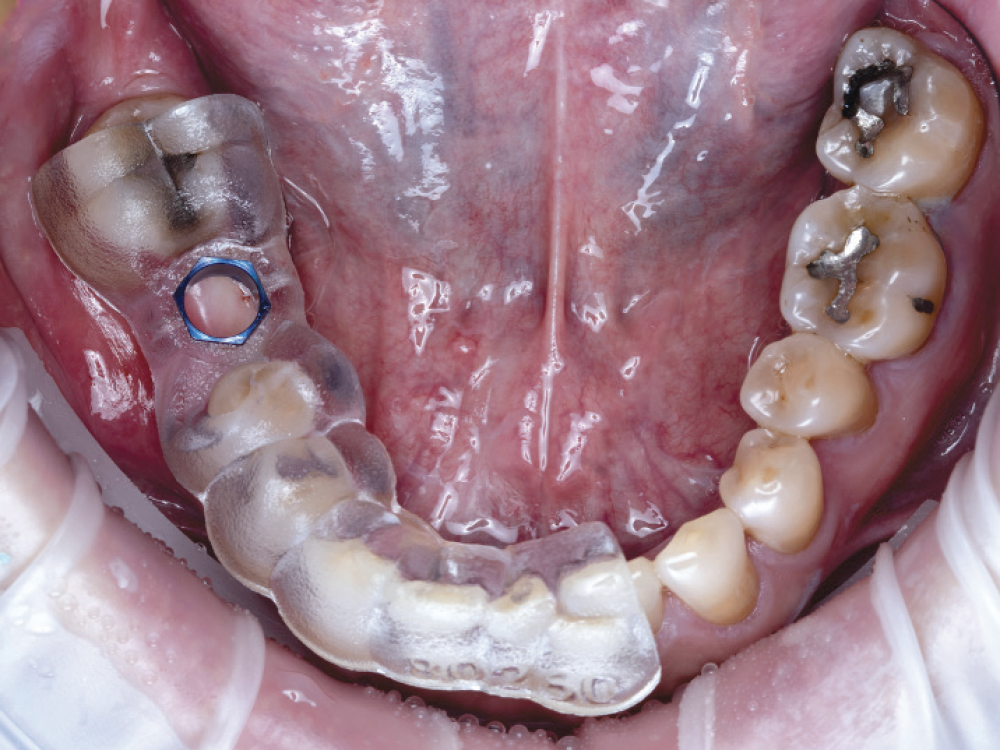

Applied Surgical Guide to Mouth

Figure 8: Prior to surgery, the surgical guide was evaluated to ensure stable fit with no rocking. The guide included a window to aid in checking the seating, as seen on the distal of #29.